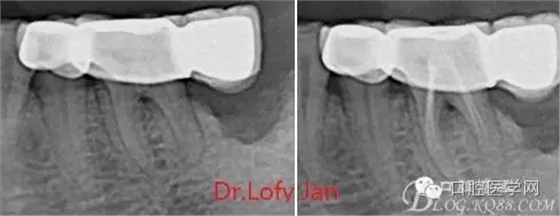

①有助于發(fā)現(xiàn)牙體和根尖周組織的異常改變,如牙折、牙內(nèi)吸收、髓腔鈣化及根尖囊腫;

②有助于確定牙根和根管的數(shù)目、位置、形態(tài)、方向和彎曲情況;

⑤評(píng)價(jià)根管充填的質(zhì)量以及療效。

病例分析:曲面斷層片在x線輔助診斷與檢查中目前大多數(shù)文獻(xiàn)和著作都建議只能作為初診拍片檢查手段,不能作為終末疾病的確診與手術(shù)療效的評(píng)價(jià)指標(biāo),臨床大部分中小型門診都因?yàn)樵O(shè)備不齊全導(dǎo)致信息偏差很大。